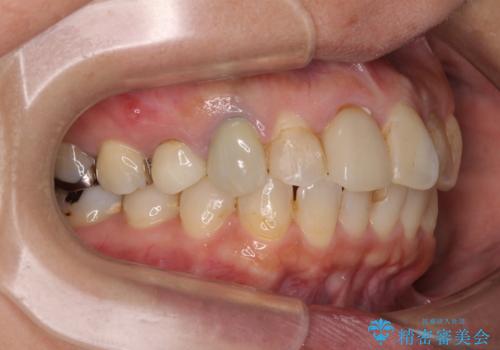

【モニター】処置歯の多い歯列 インビザラインでデコボコを整える

- 上下前歯のデコボコを気にして来院された患者様です。

歯列としては、ワイヤー装置でもインビザラインでも、どちらでも対応可能でしたが、処置されている歯が多く、ワイヤー装置を装着するためには処置歯のやり直しが必要な状態でした。

インビザラインでもアタッチメントを装着できないという同様のデメリットがありますが、比較的矯正治療を行いやすい歯列であったので、インビザラインによる矯正治療を行うこととしました。